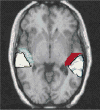

The planum temporale is a highly lateralized cortical region, located within Wernicke's area, which is thought to be involved in auditory processing, phonological processing, and language. Research has linked abnormal morphology of the planum temporale to developmental dyslexia, although results have varied in large part due to methodological inconsistencies in the literature. This study examined the asymmetry of the planum temporale in 29 children who met criteria for dyslexia and 26 children whose reading was unimpaired. Leftward asymmetry of the planum temporale was found in the total sample and this leftward asymmetry was significantly reduced in children with dyslexia. This reduced leftward asymmetry in children with dyslexia was due to a planum temporale that is larger in the right hemisphere. This study lends support to the idea that planum temporale asymmetry is altered in children with developmental dyslexia.